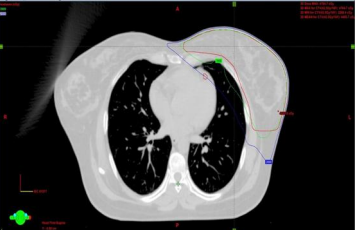

e) Radiotherapy planning

The treatment plan was carried out using a CT-based, Intensity-modulated Radiotherapy or 3-dimensional conformal radiotherapy. According to the patient’s comfortable breathing pattern, planning was done either on FB or DIBH. Beam angle modification, collimator leaf adjustment, and planning optimization are utilized to minimize LAD and heart dose. Plan evaluation was done and if satisfactory Quality assurance was done and transferred for treatment execution.

Figure 3a, Figure 3b

Figure 3: a) LAD CONTOURED AND SPARED, b) LAD CONTOURED BUT NOT SPARED

Heart and LAD dose-volume-histogram (DVH) data from both groups (ARM A, ARM B) were compared. (figure 4)

Figure 4a (Graph 1: DVH of one Retrospective patient), Figure 4b (Graph 2: DVH of one Prospective patient)